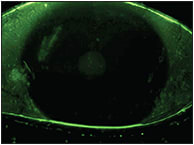

At every follow-up visit, the patient showed steady improvement in both signs and symptoms. By one month, we saw a dramatic improvement in corneal health (Figures 1 and 2). It was after two months of wear that she described her symptoms as being more than 90% improved.

Figure 1. Our patient’s cornea after several months of dry eye therapy and before scleral lens fitting.